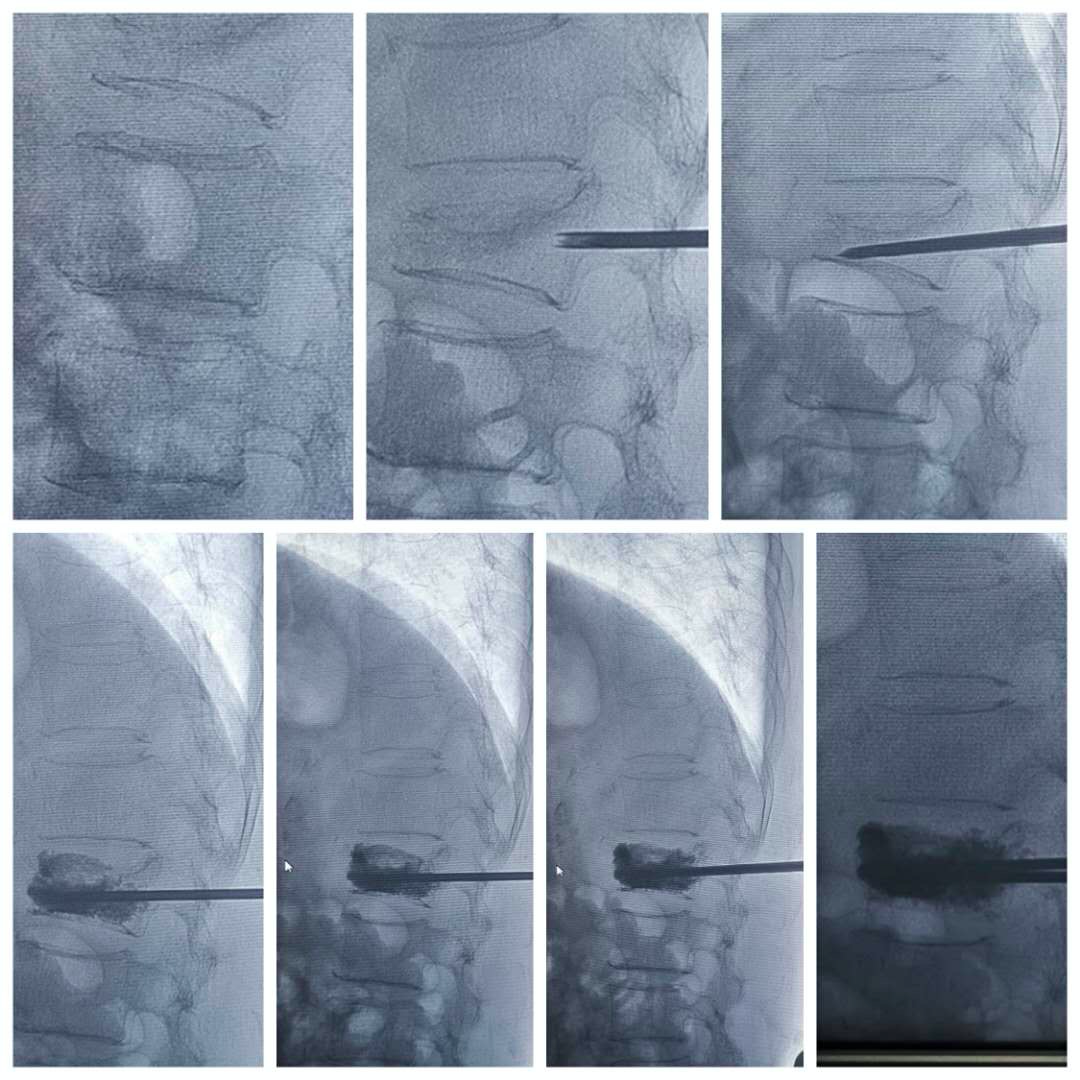

“骨水泥”的放入和穿刺,都需要考验手术团队精准高超的技巧。手术中,手术团队在张奶奶的胸背部扎一个绿豆大的小孔,在C臂X光机视频的引导下,将穿刺针精确地置入病椎,然后注入高粘度骨水泥,使椎体恢复足够的高度和强度。手术非常顺利,仅用20分钟就顺利完成了。

▲术中连续拍片,可见压缩椎体逐步复位良好